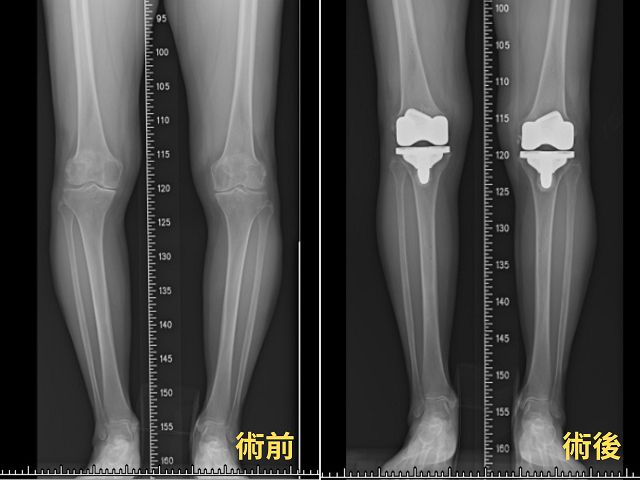

陳女士說,她的膝關節庝痛已持續7、8年,之前還能勉強忍受,但在去年底的一次健行爬山中痛到完全無法行走,透過朋友介紹,前往長安醫院骨科尋求幫助。楊醫師檢查後發現,她的退化性關節炎已屬於第四期,並且已經出現O型腿的變形,經過討論後,決定接受恢復比較快的微創機器手臂關節置換術。

楊志鴻醫師表示,精準定位是膝關節置換手術成功的關鍵,而這正是Mako®機器手臂的優勢所在。它能根據患者的膝關節角度及下肢軸線,精確設計出最適合的人工關節尺寸及擺放位置。與傳統手術相比,Mako®機器手臂不僅能縮小手術傷口,還能保留健康的骨本和韌帶組織,使患者術後恢復更快。

手術進行得非常順利,僅用三個小時就完成了雙膝人工關節置換。術後第二天,陳女士就能下床行走;第三天,她已經完全不需要拐杖輔助,能在走廊來回走動;40天後,更是能在山林間步行自如。她感謝楊醫師的精湛技術,開心直呼手術後「讓我的人生變回彩色的」。